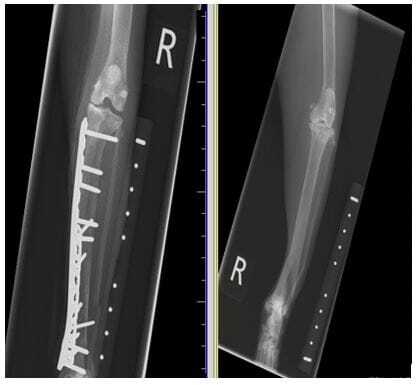

Compression is achieved through the use of a dynamic compression plate (DCP) and a specific DCP drill guide. When used with the gold “loaded” end of the drill guide, the hole is drilled off centre (away from the fracture) and so, when the screw is placed and it is forced into the centre of the hole (due to the design of the hole having a slope to force the screw into the centre of the hole), this compresses the fracture ends together. The neutral end of the drill guide can be used when compression isn’t required ( Figure 2; Farrell, 2016) Some locking plates can also have this design, giving the surgeon the option of using them to compress or not. Compression can only be achieved successfully if the fracture fragments are reduced fully and well aligned. With this method, the load on the bone post-operatively is shared between the bone and the plate ( Figure 3; Conzemius and Swainson, 1999)

FIGURE (3) This fracture was repaired under compression, as you can see the two ends of the fracture are accurately aligned